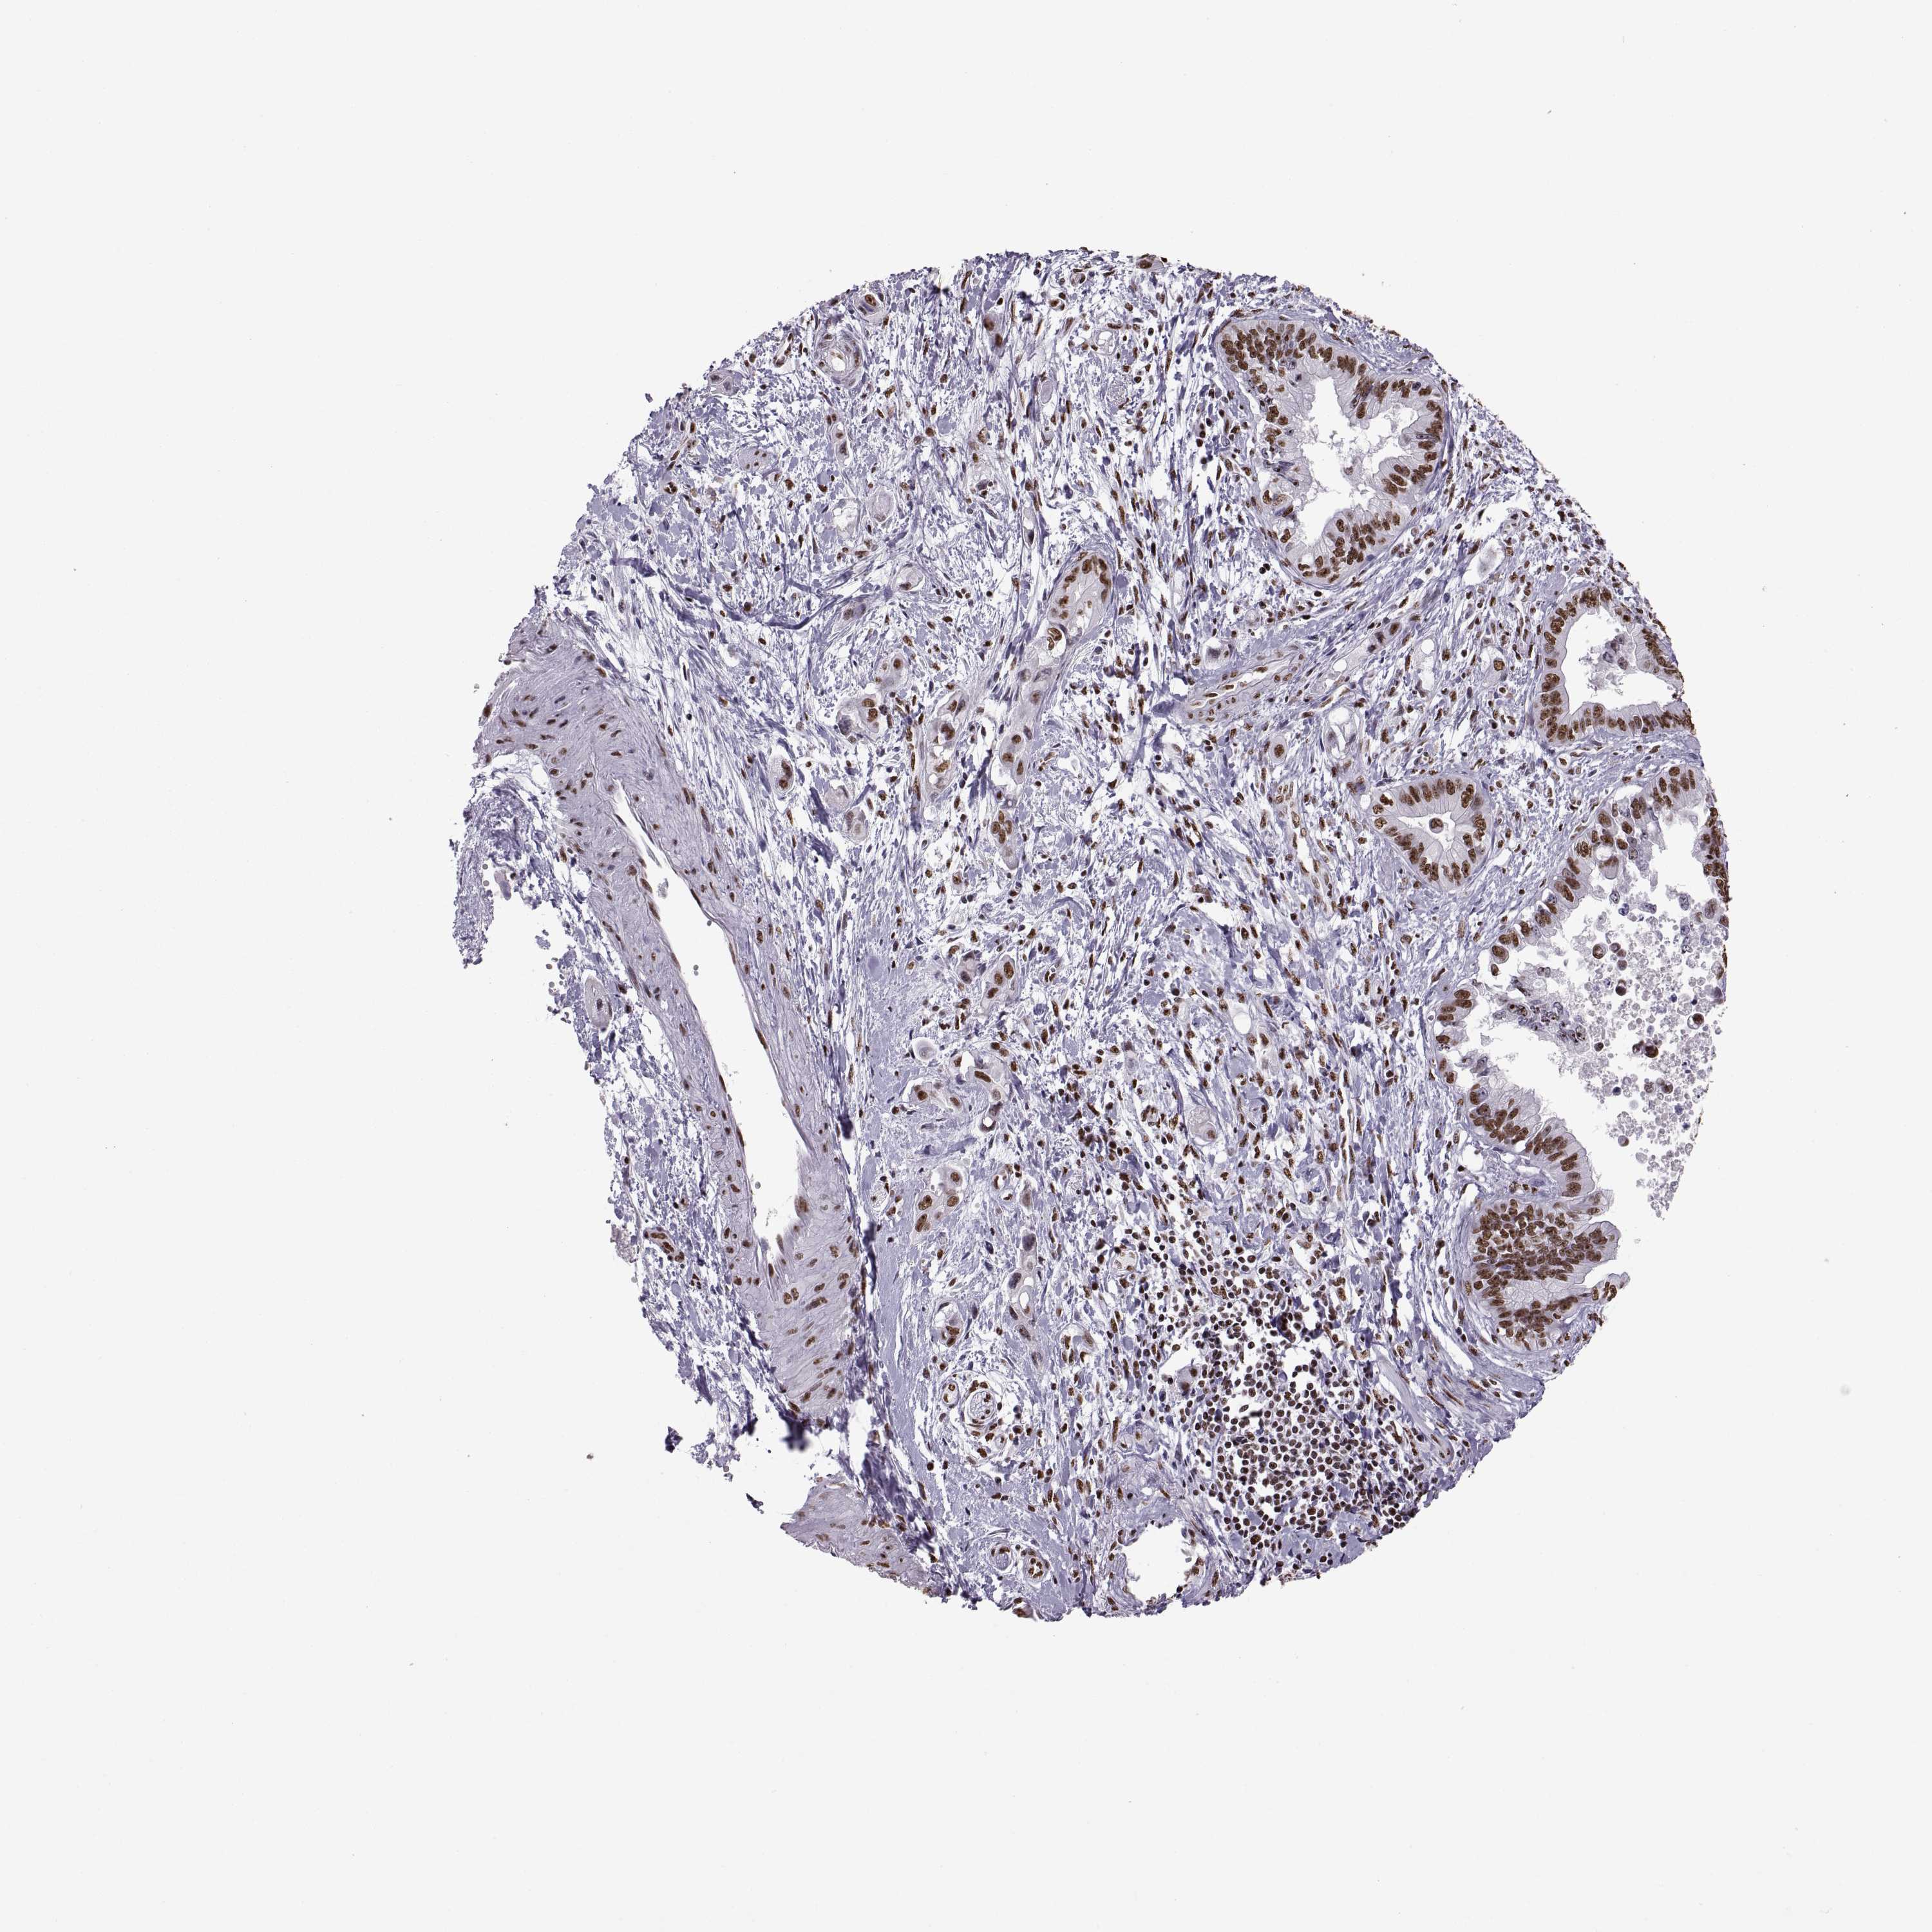

PANCREATIC CANCER - Protein expressioni

A mouse-over function shows sample information and annotation data. Click on an image to view it in a full screen mode. Samples can be filtered based on level of antibody staining by selecting one or several of the following categories: high, medium, low and not detected. The assay and annotation is described here.

Note that samples used for immunohistochemistry by the Human Protein Atlas do not correspond to samples in the TCGA dataset.

Antibody stainingi

Antibody staining in the annotated cell types in the current human tissue is reported as not detected, low, medium, or high, based on conventional immunohistochemistry profiling in selected tissues. This score is based on the combination of the staining intensity and fraction of stained cells.

Each image is clickable and will lead to virtual microscopy that enables deeper exploration of all samples and also displays staining intensity scores, fraction scores and subcellular localization as well as patient and tissue information for each sample.

Antibody HPA069985

Antibody CAB005883

Antibody CAB078687

Antibody CAB080398

Staining

High

Medium

Low

Not detected

Intensity

Strong

Moderate

Weak

Negative

Quantity

>75%

75%-25%

<25%

None

Location

Nuclear

Cytoplasmic/membranous

Cytoplasmic/membranous,nuclear

Adenocarcinoma, NOS

Adenocarcinoma, metastatic, NOS